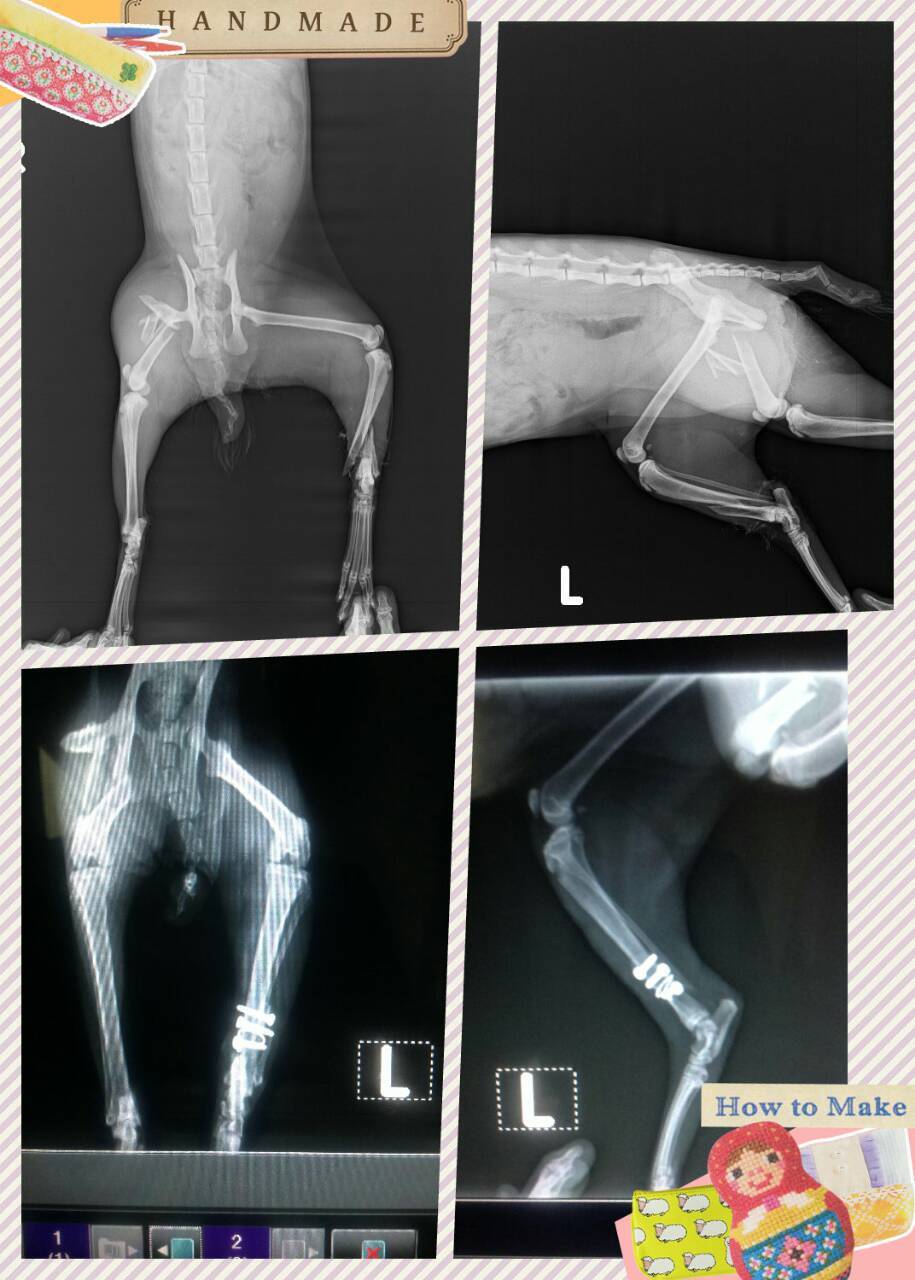

主題: 民族路的車禍癱瘓貓 申請者姓名: 劉素鳳 花色: 申請日期: 2015-05-15 16:47:38 申請者部落格: 申請者臉書網址: 劉素鳳 所在縣市/合作醫院: 高雄市/銀星動物醫院 治療費用: 27900元 需求人數: 30人 已結案 (2022-03-11 00:09:04) 報名人員: Nil Lin(已付款)、陳薏絜(已付款)、Jolie(已付款)、竹君(已付款)、Kenix(已付款)、Cathy Chang(已付款)、張瑞芬 x2(已付款)、vivian(已付款)、vita yang(已付款)、張恩綺(已付款)、林俞彤(已付款)、PhoebeWang(已付款)、Alison Lee(已付款)、家有三色喵(已付款)、Haru chen(已付款)、櫻花妹(已付款)、Alice(已付款)、Alice(已付款)、annlin(已付款)、Rocky Chen x2(已付款)、Egg Sh(已付款)、坤仔、坤仔(已付款)、史蒂芬(已付款)、阿偉(已付款)、張雅筑(已付款)、孟星魂 x2(已付款)、Felina Liu(已付款)、Ying-chen Chiu(已付款)、 候補人員: 動物病情說明: 這是行經六合夜市旁的民族路邊看到的疑似車禍貓,後兩腳拖行,送醫檢查貓咪後兩腳是粉脆性骨折,神經還有反應,治療希望腳有復原的機會。一開始進院貓咪狀況沒有很穩定,且有發燒的狀況,骨折處傷口感染,所以先穩定貓咪狀況,接下來等狀況較穩定,先處理開放性骨折的患肢,右腳雖還沒手術但已可以活動,有希望能逐漸恢復活動力,故先暫緩手術。

由於之前左後肢開放性骨折傷口,手術後傷口有感染狀況,有再清創過一次,但感染情況沒有控制住,於是決定於進行截肢手術,避免傷口向上感染,後來傷口狀況穩定。最後傷口剩下一小塊肉芽組織還沒癒合,其他傷口接癒合好,食慾精神都正常,右腳已可使用,後來停止針劑,只有口服藥跟清創抹藥,再修養一些時間準備出院。